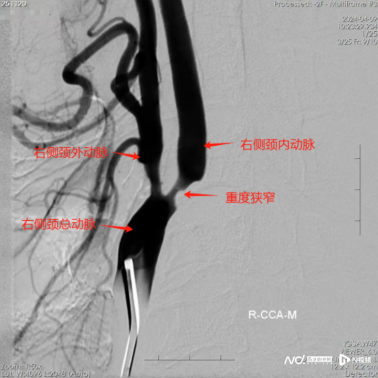

该院神经外七科主任吾太华接诊了患者。完善相关检查提示患者的左侧颈内动脉狭窄程度达75%。如果不及时手术,还可能会反复诱发脑梗死,患者说话、行动会进一步受到影响。

术前、术后影像对比。